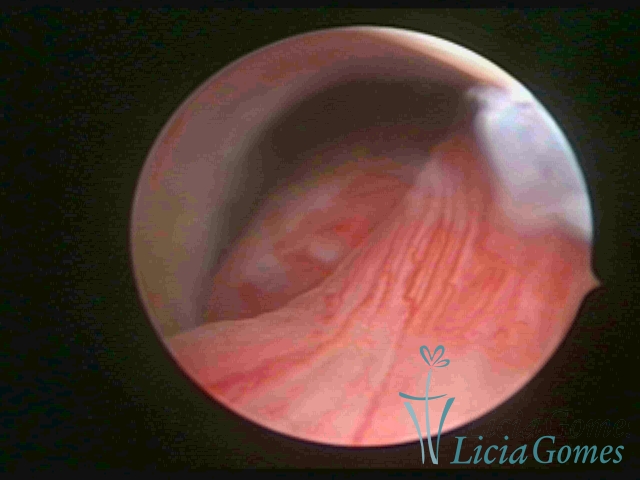

PÓLIPOS ENDOCERVICAIS

São tumores benignos, resultantes da proliferação focal reativa aos processos inflamatórios ou à situações de hiperestrogenismo, e podem ter sésseis (com a base de implantação larga) ou pediculados do epitélio.